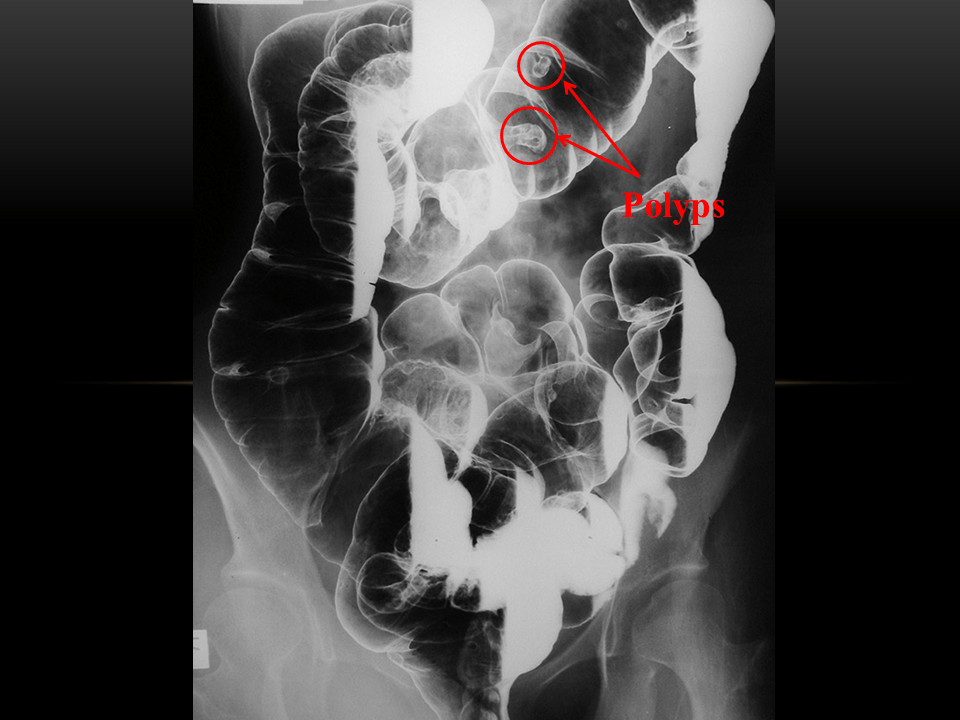

From www.slideshare.net

Intestinal polyps What Is A Hepatic Flexure Polyp It can appear in many different locations in. Inflammatory fibroid polyp (ifp) is a rare benign polypoid lesion of the gastrointestinal tract. It is close to the liver, hence the name. For example, hyperplastic polyps are typically benign. This is the sharp bend between the ascending colon and the transverse colon. Polyps are growths on the inner lining of the. What Is A Hepatic Flexure Polyp.